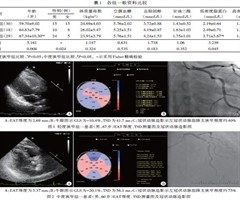

心外膜脂肪组织厚度联合左心室应变达峰时间离散度预测冠状动脉狭窄程度的临床价值

摘 要 目的 应用超声心动图检测心外膜脂肪组织(EAT)厚度、左心室纵向应变达峰时间离散度(TSD),探讨二者联合应用预测冠状动脉狭窄程度的临床价值。方法 选取我院因胸痛、胸闷行冠状动脉造影的患者77例,根据其冠状动脉狭窄...